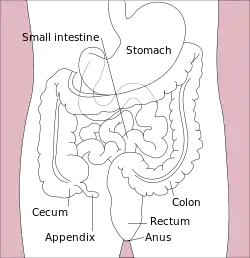

Appendicitis is inflammation of the appendix.[2] Symptoms commonly include right lower abdominal pain, nausea, vomiting, and decreased appetite.[2] However, approximately 40% of people do not have these typical symptoms.[2] Severe complications of a ruptured appendix include widespread, painful inflammation of the inner lining of the abdominal wall and sepsis.[3]

Appendicitis is primarily caused by a blockage of the hollow portion in the appendix.[10] This blockage typically results from a calcified "stone" made of feces.[6] Other factors such as inflamed lymphoid tissue from a viral infection, intestinal parasites, gallstone, or tumors may also lead to this blockage.[6] When the appendix becomes blocked, it experiences increased pressure, reduced blood flow, and bacterial growth, resulting in inflammation.[6][11] This combination of factors causes tissue injury and, ultimately, tissue death.[12] If this process is left untreated, it can lead to the appendix rupturing, which releases bacteria into the abdominal cavity, potentially leading to severe complications.[12][13]